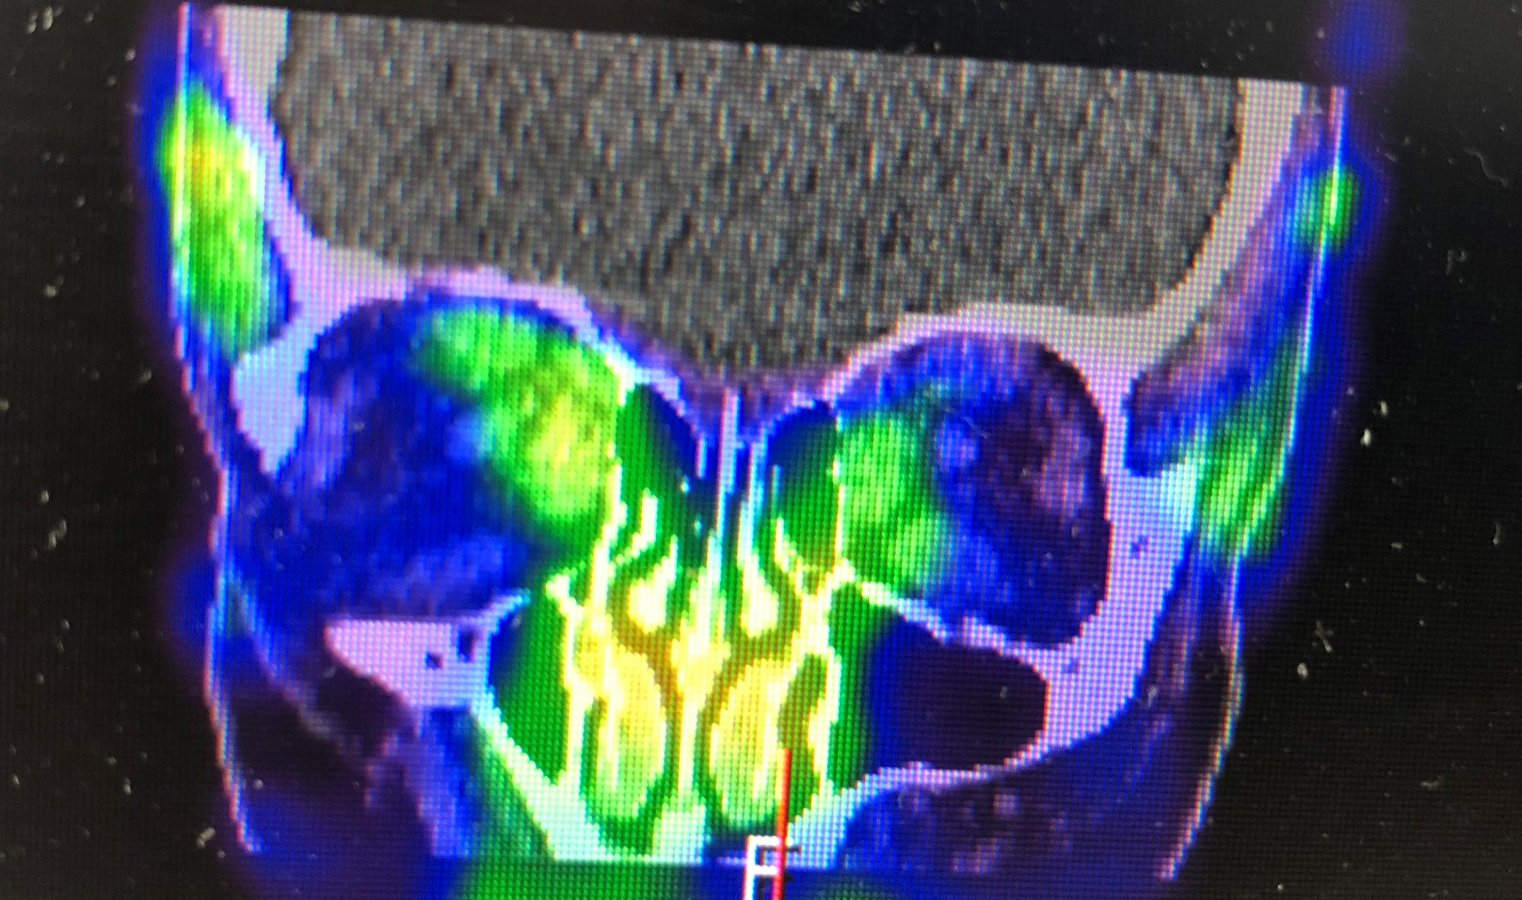

Przykładowe obrazy scyntygraficzne uzyskiwane w naszym Zakładzie Medycyny Nuklearnej: